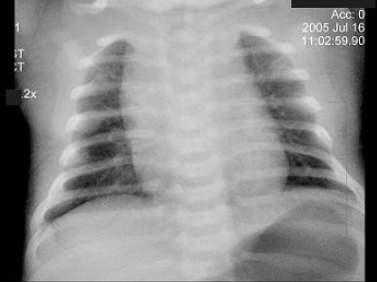

77、单项选择题

男,根据其正常骨盆影像图像,判断其最可能的年龄()

A.6岁左右

B.30岁左右

C.12岁左右

D.18岁左右

E.24岁左右

89、单项选择题

男,根据其正常盆腔影像图像,判断其最可能的年龄()

A.10岁左右

C.20岁左右

D.80岁左右

E.60岁左右

130、单项选择题

A.1岁左右

B.4岁左右

C.7岁左右

D.10岁左右

E.13岁左右